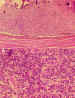

El Retinoblastoma indiferenciado está compuesto por una proliferación

difusa en sábana de células semejantes a las de la retina embrionaria que no

muestran evidencia de maduración. Son células pequeñas, redondas o

poligonales, con núcleos hipercromáticos, irregulares frecuentemente en

mitosis a veces de carácter atípico y escaso citoplasma (figura 4).

Figura 4. Retinoblastoma indiferenciado. Proliferación celular

difusa con atipia citológica y ausencia de diferenciación. H.E. (400x).